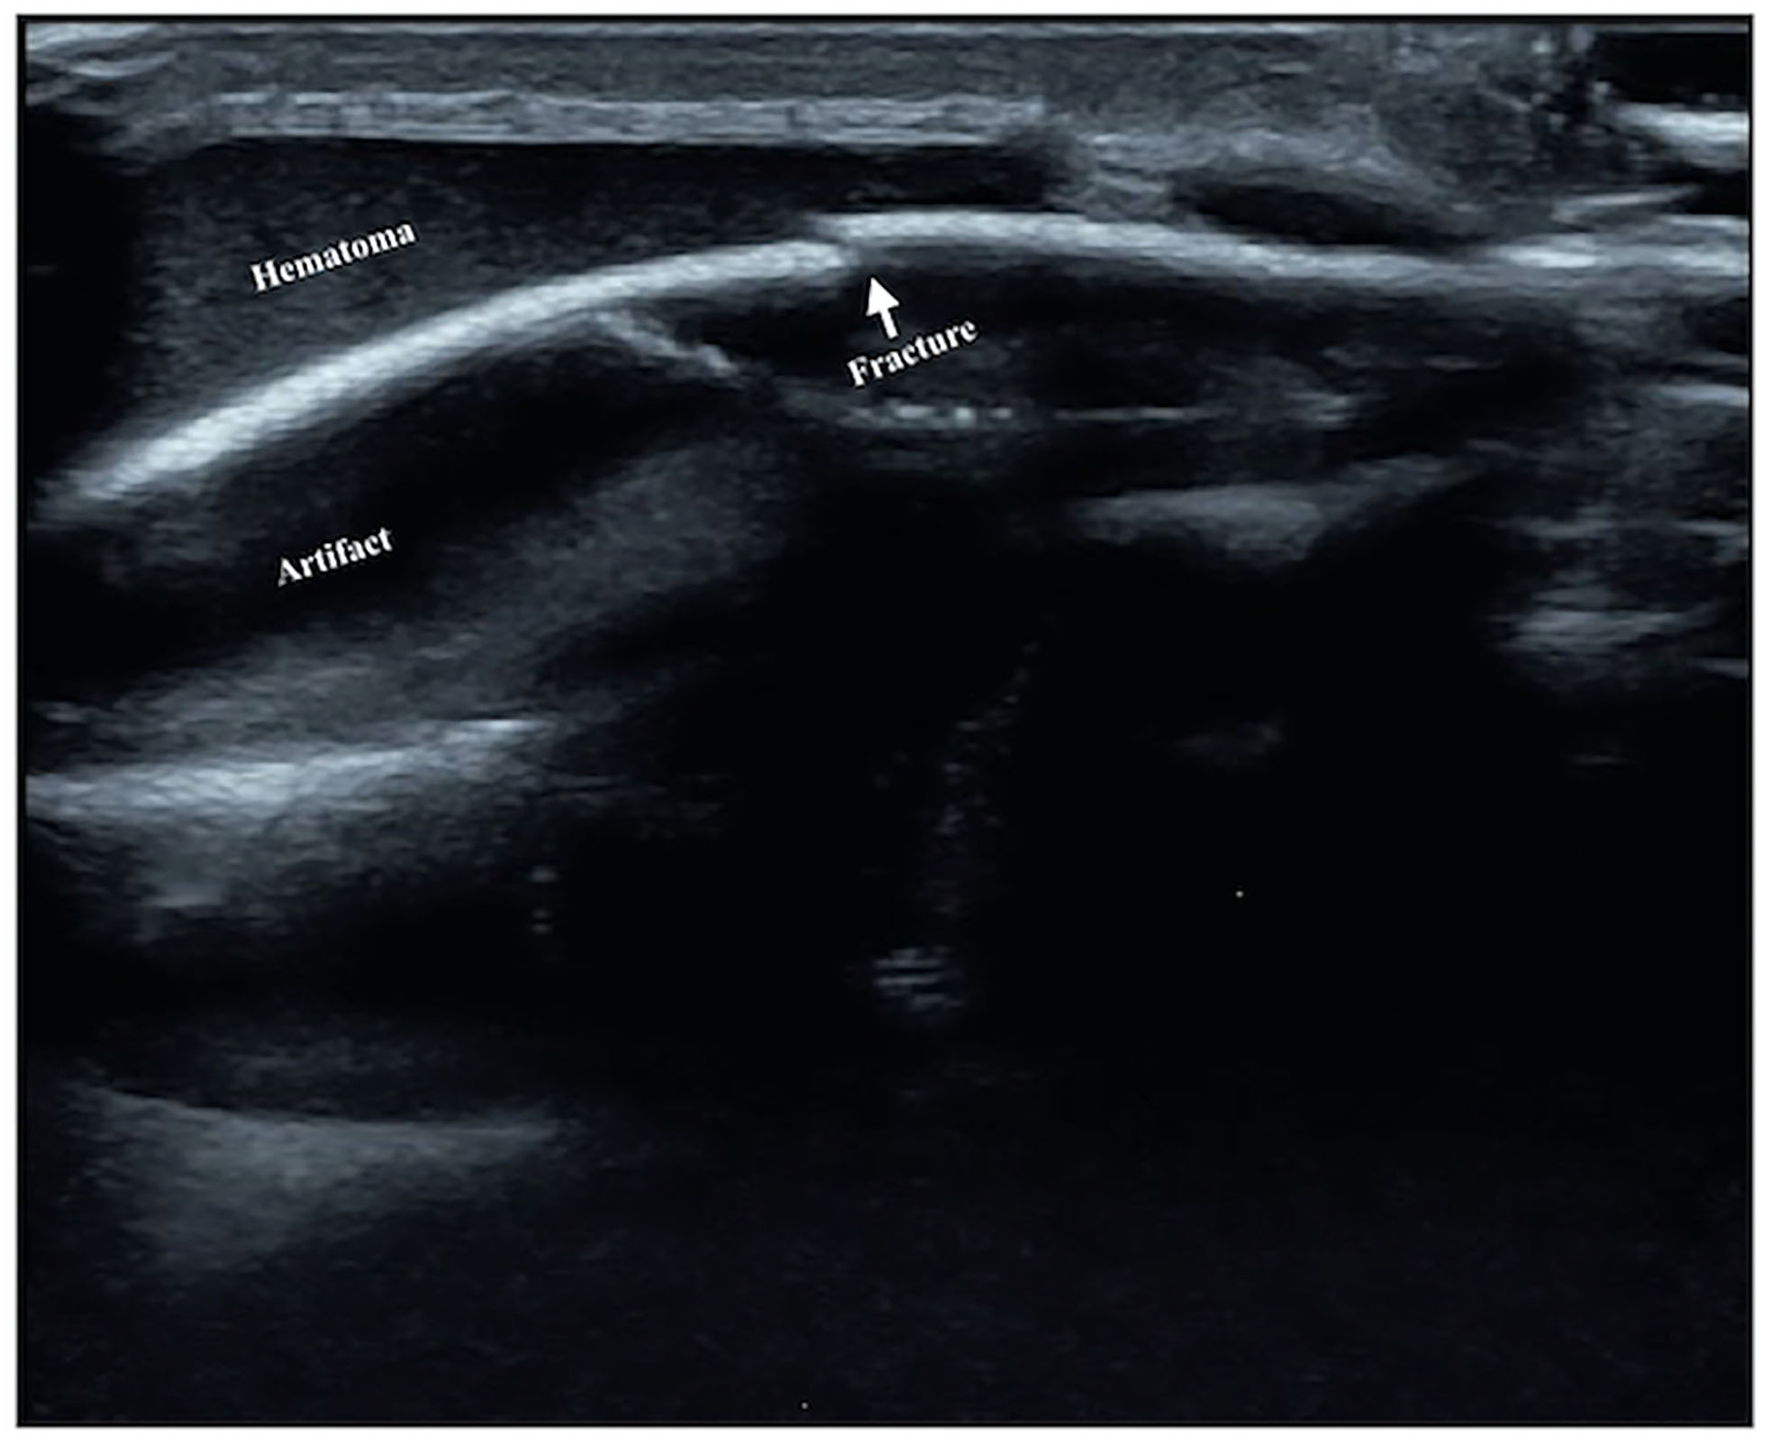

Figure 5

Rib fracture. The infant was G3P1, with a gestational age of 30+1 weeks and a birth weight of 1,370 g. The infant was born by Cesarean section due to placental abruption. After birth, the infant suffered from various diseases, such as respiratory distress syndrome, pneumonia, atelectasis, and calcium and phosphorus metabolism disorder, which was diagnosed as metabolic bone disease. Forty days after birth, an ultrasound examination found that the infant had a fracture in the fifth rib on the left side.

Figure 6

Skull fracture. The infant is G1P1 with a gestational age of 39+2 weeks, vaginal delivery, and birth weight of 3,940 g. He suffered from severe asphyxia at birth and was diagnosed with HIE and cranial hematoma on the top of the left head on admission. Brain ultrasound revealed that the continuity of the skull bone under the hematoma was interrupted, and the formation of broken ends with slight dislocation and separation was seen, which suggested the presence of a skull fracture.